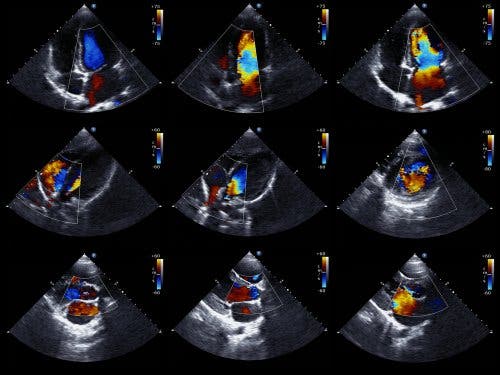

L’échocardiogramme est la preuve préférentielle pour détecter un épanchement péricardique. On parle aussi d’échocardiographie ou d’ultrasons cardiaques. C’est un test qui permet de visualiser la structure du cœur et d’étudier sa capacité à pomper du sang.

L’échocardiogramme réalisé selon la technique Doppler permet aussi d’établir la vitesse exacte des flux du cœur. Du point de vue technique, l’échocardiogramme bidimensionnel et en mode M est la technique idoine pour diagnostiquer, quantifier et faire un suivi de l’épanchement péricardique.

L’inexistence d’échos entre l’épicarde et le péricarde latéral est une découverte qui permet de diagnostiquer un épanchement péricardique. Le cardiologue déterminera la taille de l’épanchement à partir de la quantité d’espace qu’il y a entre les deux couches du péricarde.

Il faut noter qu’il existe deux types d’échocardiogramme. Le transthoracique, dans lequel on emploie un dispositif qui se pose sur le torse, à la hauteur du cœur, et émet du son. Et l’échographie trans-œsophagienne, dans laquelle le dispositif s’introduit dans le tube digestif jusqu’à l’œsophage. Cette dernière apporte des données plus détaillés.